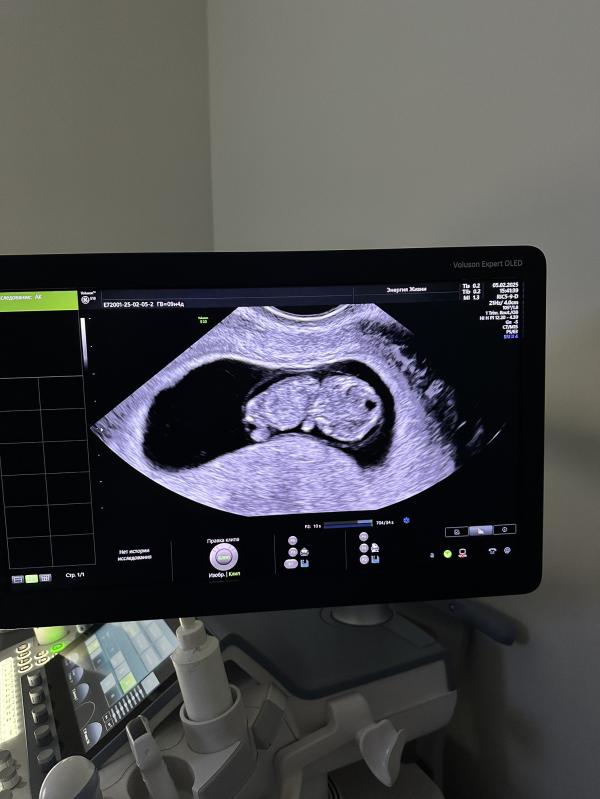

В общем зря наводила «панику» с этими симптомами 😀 и хгч в порядке, а на узи так вообще прекрасно растем 🤞

Разглядели сегодня все что могли 🙂 , мозг, сердце, позвоночник, уши, ручки с ножками и даже пальчики 🥹 эмоции не передать… 🥰

на снимок (последнее фото) удалось запечатлить ручку с пальчиками ✌️😅